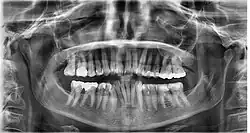

Ein Orthopantomogramm (OPT oder OPG, seltener OPTG), auch Panoramaschichtaufnahme (PSA) genannt, ist eine zweidimensionale Röntgenaufnahme des Ober- und Unterkiefers in Form eines Halbkreises von einem Ohr zum anderen. Es ist ein Standardverfahren der dentalen Radiographie und erlaubt eine diagnostische Röntgenaufnahme der Ober- und Unterkiefer des Menschen, dabei werden alle Zähne, die angrenzenden Kieferbereiche, beide Kiefergelenke und ebenso die rechte und die linke Kieferhöhle abgebildet. Das OPT erfasst ferner den seitlichen Halsbereich, so dass auch Arterienverkalkungen der großen Halsschlagadern diagnostizierbar sind.

In erster Linie dienen OPG-Aufnahmen der Übersicht, demnach einer Grobdiagnostik, beispielsweise ob Zähne verlagert, retiniert oder nicht angelegt sind. Auch Veränderungen des Kieferknochens sind erkennbar und oft der Verlauf des Nervus mandibularis. Zahlreiche Nebenbefunde können erfasst werden. Der mittlere Bereich der Aufnahme wird durch eine verfahrenstechnisch bedingte Überprojektion der Halswirbelsäule speziell im Frontzahnbereich verschattet. Ebenso werden oft die Wurzelspitzen durch eine Überprojektion des knöchernen Gaumens verschattet. Dadurch sind diese Bereiche undeutlich abgebildet und einer präzisen Diagnostik nicht zugänglich.[6]